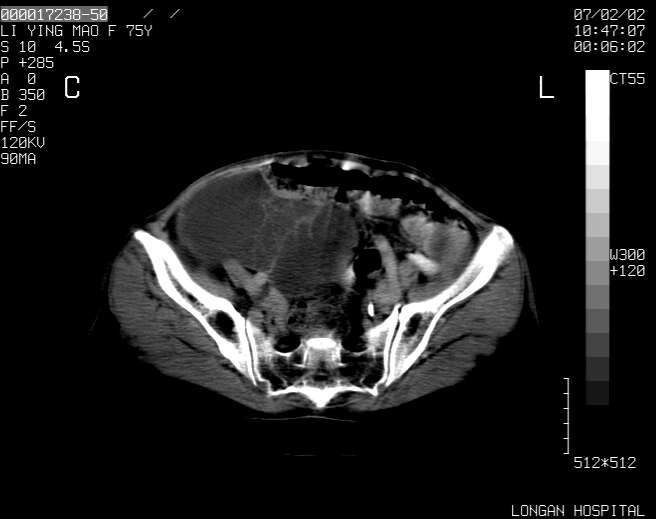

以下是引用dyqct在2007-2-10 8:53:00的发言:[br]考虑:1、肝脏多发囊肿[br] 2、左肾囊肿,右肾多发结石并积水。[br] 3、右胸少量积液。[br] 4、右肾周包裹性积液或淋巴管瘤(有见缝就钻的征象、薄隔、小结节状钙化)?[br] 5、腰椎动脉瘤样骨囊肿?[br] [br] [br]